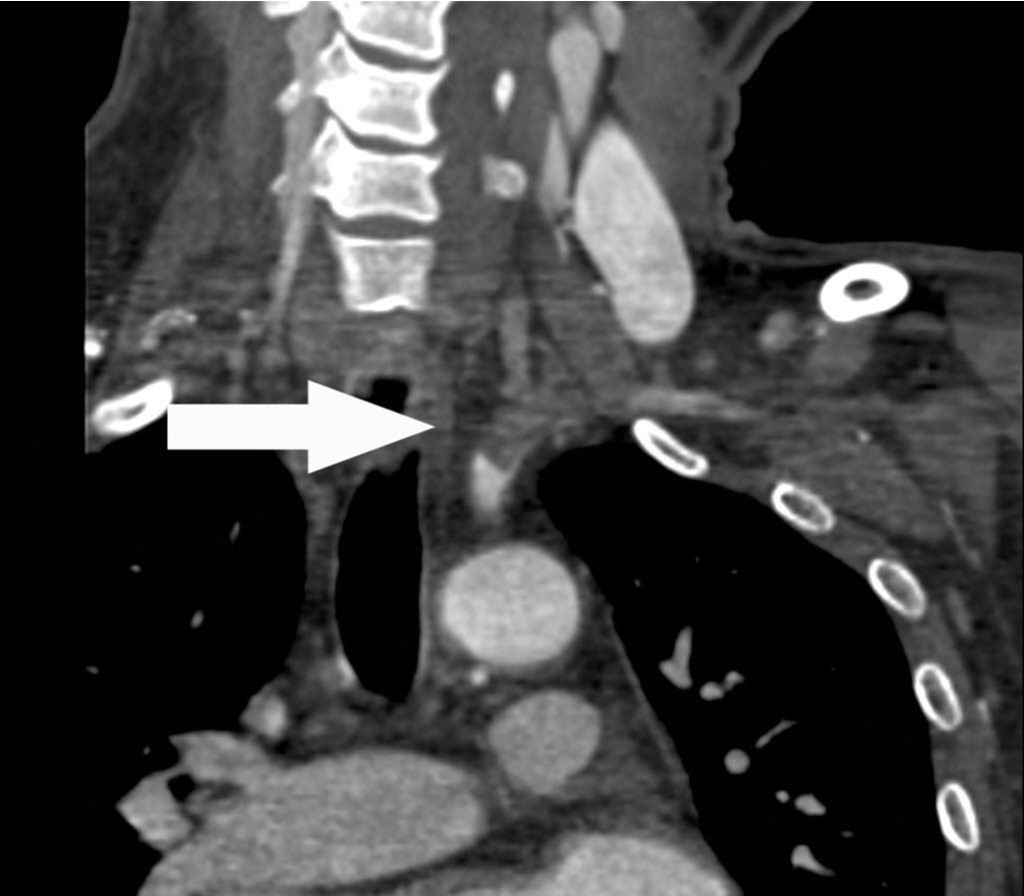

상지 CT 혈관조영술 관상면 영상에서 좌측 쇄골하동맥의 근위부에서 약 7cm에 걸쳐 혈전색전증에 의한 혈관의 부분폐쇄가 확인되고(Fig. 1A, B, C), 혈전색전증은 좌측 추골동맥 근위부로도 연장되어 있음(Fig. 1D).

Fig. 1. A-D

Fig. 1A-D Coronal CT images show a partial thrombotic occlusion at proximal subclavian artery (SCA, arrow in Fig. 1A-C), and proximal vertebral artery (VA, arrow head in Fig. 1D).